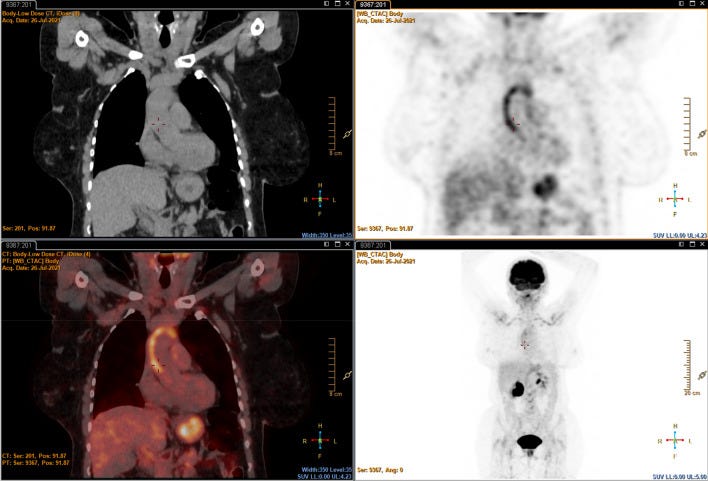

‘report a case of large vessel vasculitis (LVV) in patient who received the first dose of mRNA COVID-19 vaccine (BNT162b2—Pfizer-BioNTech). A 63-year-old woman with a personal history of hypertension has been observed at the end of June 2021 to a tertiary-care center (San Carlo Hospital), in Basilicata region (Italy). The day following the first vaccination (May 2021), she experienced fatigue, myalgias and after 5 days she rapidly developed fatigue as well as low grade fevers, anorexia, and headache. Over the next 4 weeks she complained a 15 lb weight loss and polymyalgia rheumatica (PMR)– like symptoms (fatigue, arthralgia, stiffness of upper arms, shoulders and neck). She denied previous similar episodes or recent infectious diseases including COVID-19; a molecular diagnostic test for COVID-19 was also performed, and was negative. Physical examination showed limitation on the range of motion about the shoulders (inability to actively abduct the shoulders past 90 degrees) and the cervical spine.’

Positron emission tomography (PET) that demonstrated an increased fluorodeoxyglucose (FDG) vascular uptake compatible with large-vessels vasculitis